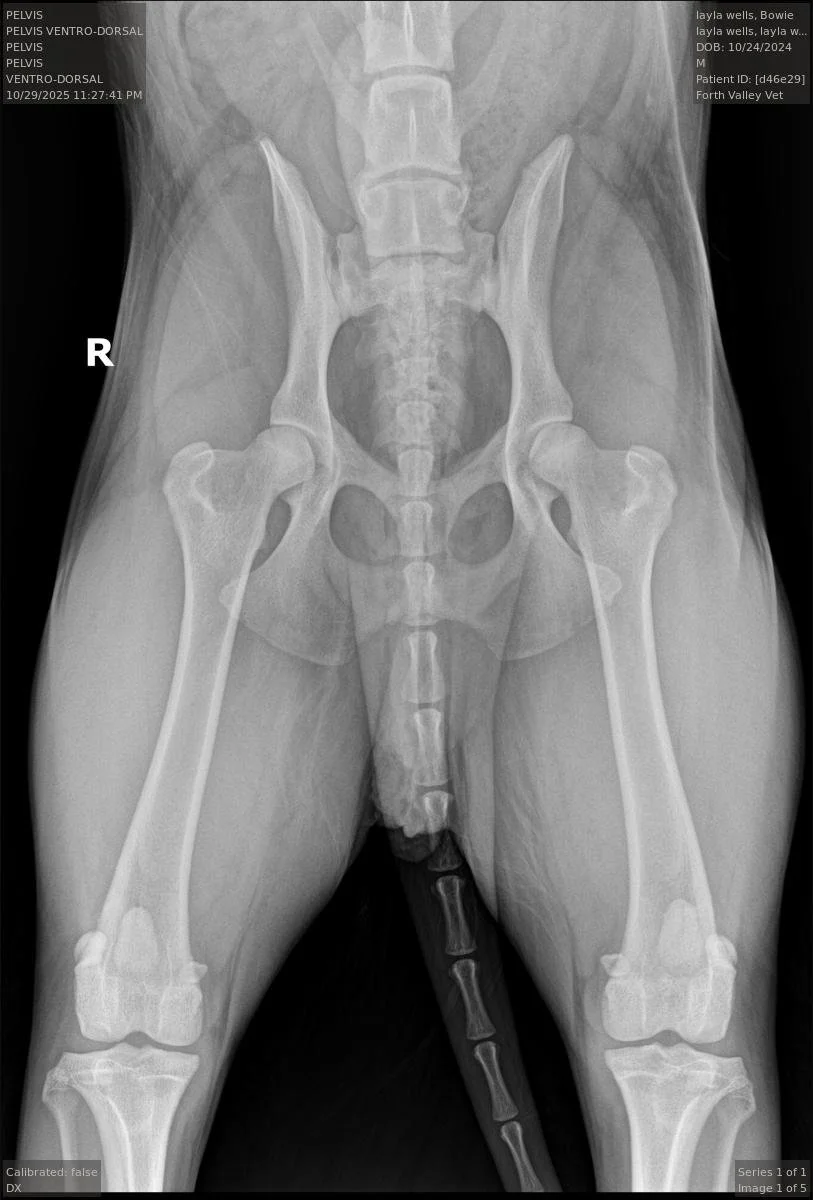

The Compression View: To see how well the hip fits into the socket.

It uses three specialized views, a distraction view, a compression view and the standard hip-extended view to provide a much more accurate and quantitative measurement than traditional methods.